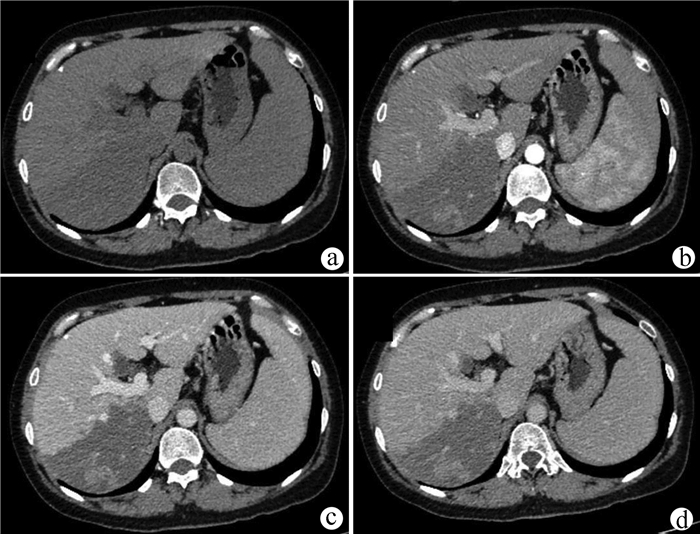

Recurrence after hepatectomy for primary gastrointestinal stromal tumor of the liver: A case report

Kangwei LIU, Xin GENG, Lei WANG, Cijun PENG

2021, 37(12): 2893-2895. DOI: 10.3969/j.issn.1001-5256.2021.12.031

Abstract(971) HTML (239) PDF (2357KB)(56)

Abstract: